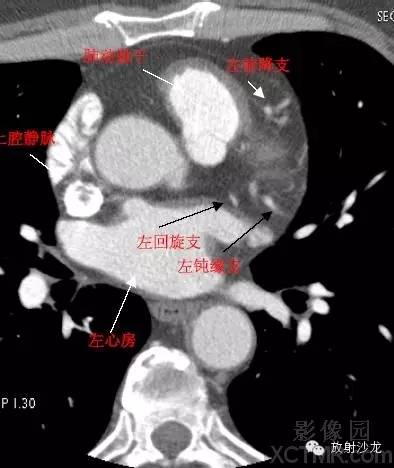

LMA -Left Main Artery冠状动脉左主干

LAD -Left Anterior Descending Artery左前降支

LCX -Left Circumflex Artery左回旋支

LMB -Left Obtuse Marginal Branch 左边缘支(钝缘支)

LAA –Left AtrialAppendage左心耳